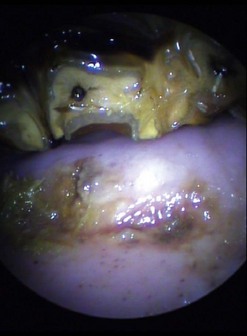

Ulceration of a caudal pharyngeal soft tissue pillar is a not uncommon sequel of dental ‘floating’. The soft tissues at this site are in very close proximity to the occlusal surface of the caudal mandibular cheek teeth (Fig. 9.10). Trauma may occur if excessive caudal movement of the rasp blade occurs during manual rasping of the last mandibular cheek tooth (311, 411), or if soft tissue becomes trapped between the tooth and rasp blade or motorized burr. Ulceration can vary in severity, and although clinical signs are generally self-limiting, affected horses may demonstrate oral dysphagia until healing occurs, which can be days or even weeks later. Systemic antibiotic and anti-inflammatory therapy is indicated with more severe injuries.

image

Fig. 9.10 Close proximity of caudal soft tissue pillar to occlusal surface of last mandibular cheek tooth (tooth 311).